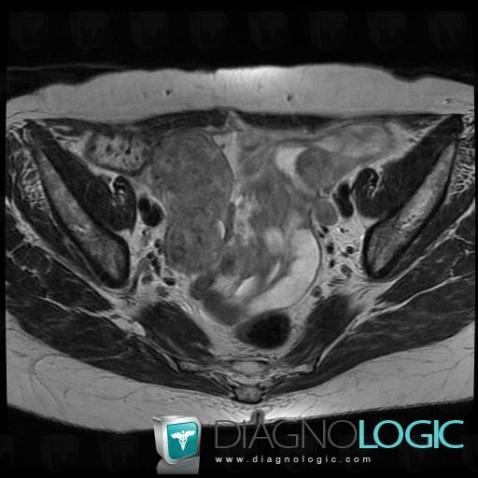

Serous cysteadenocarcinoma, Adnexa / Ovary fallopian tube, Pelvis / Perineum, MRI

Here is the specific information in the key image above:

- Diagnosis Serous cysteadenocarcinoma (link to Serous ovarian tumor), Location(s) Pelvis / Perineum, with gamuts Complex pelvic massAdnexa / Ovary fallopian tube, with gamuts Complex adnexal mass